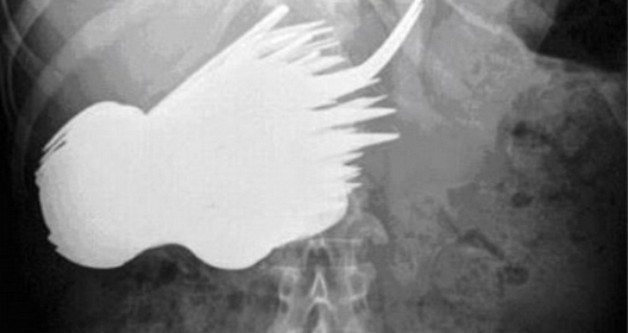

insan-ameliyat-esya11- Mideden çıkan 4.5 kiloluk saç yığını

Fotoğrafta gördüğünüz şey, bir insanın midesinden çıkartılan, 4.5 kilo ağırlığında bir saç yığını. 18 yaşındaki adı açıklanmayan bir genç kız, trikofaji olarak da bilinen saç yeme hastalığına yakalanmıştı. Midesinde ağrı ve yemek yedikten sonra kusma şikayetiyle doktora giden genç kız, çok fazla kilo kaybettiğini de söylemişti. Saçların çıkartılması sonrası genç kız tamamen iyileşti ve bir süre sonra bu alışkanlığı bir kenara bıraktı.